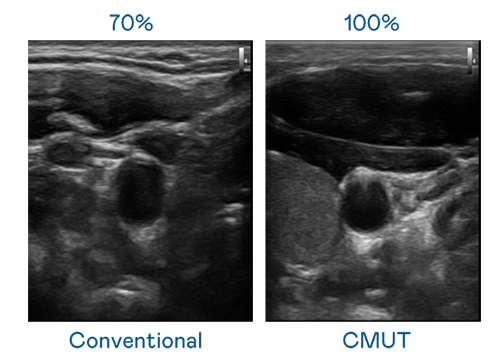

CMUT 技术是一种用电容式微机电元件来产生超音波讯号的技术。与传统 PZT 压电式技术相比,CMUT 频宽增加 30%,更宽频的超音波讯号让影像解析度大幅提升,是实现高影像品质医疗超音波扫描、促进精准医疗发展的关键技术。

大频宽带来超清晰影像

超音波影像的解析度高低,首先取决于探头能发出的讯号频宽。304永利集团 CMUT 可提供高清晰的超音波讯号,提供高频宽、高灵敏度、影像纹理细节更高的超音波影像,协助医护人员缩短影像判读时间及利用精准的医疗影像进行诊断。